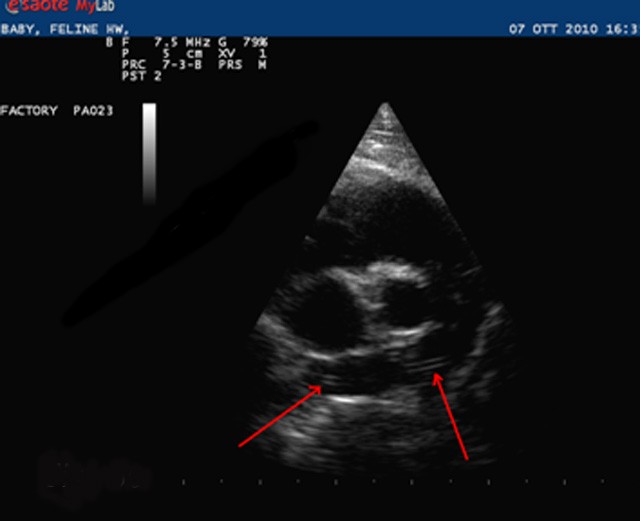

Ecografia este o metodă de diagnostic esențială, fiind complet nedureroasă și neinvazivă pentru animalul tău. Fie că este vorba despre o ecografie abdominală la câini sau o investigație preventivă pentru pisica ta, această metodă ne permite să vizualizăm organele interne în timp real fără a recurge la sedare în majoritatea cazurilor. La clinica noastră, punem accent pe un diagnostic corect la un preț accesibil, oferind siguranța că fiecare detaliu este analizat cu atenție pentru a depista precoce eventualele afecțiuni interne.

• Analiza detaliată a organelor (ficat, rinichi, vezică)